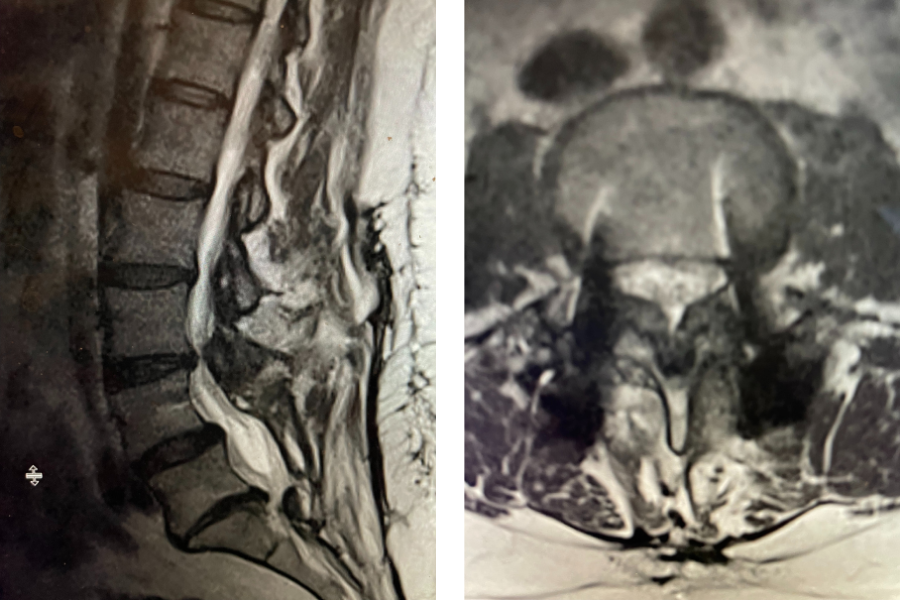

Fig 1: Sagittal and axial T2-weighted lumbar MRI demonstrating severe L4-5 Stenosis and grade 1 spondylolisthesis. Note (yellow arrow) cystic anteromedial extension off the right facet joint causing right-sided lateral recess cut-off of thecal sac and compression of the right L5 nerve root.

This 70 year-old male with two years of right leg pain with minimal low back pain. The patient had tried physical therapy and epidural injections. Neurologically he was intact. MRI revealed a grade 1 spondylolisthesis (slipped spine in Greek) at L4-5 with severe lumbar stenosis mainly due to thickened yellow ligament and overgrown joints; but the thing that I believe put him over the edge was a small joint cyst on the right (Fig 1). People just form cysts. You can get a cyst in practically every organ including kidney, liver, ovarian, etc. People are actually fascinated by them. When patients have spine surgery the only thing that matters to them is, “did you get the cyst?” The fact is that they are these small gelatinous balls that come off the joint space and grow into the spinal canal and cause symptoms by compressing the nerve. You essentially bite them away with our instruments. You really can’t aspirate them through the skin. They are just a form of arthritis and are always benign.